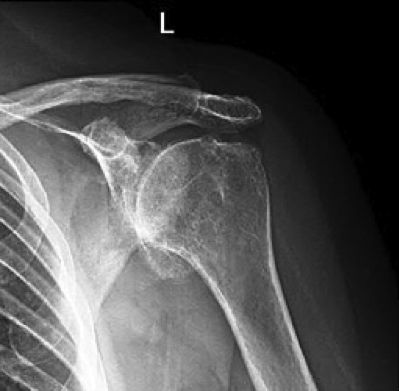

ARTROSIS DEL HOMBRO

La Artrosis es una enfermedad degenerativa de las articulaciones. Básicamente consiste en la pérdida del cartílago articular, la formación de osteofitos (picos de hueso) y la deformación de la articulación afectada. El cartílago hialino de las articulaciones es una capa de unos milímetros de un tejido conectivo especializado en absorber carga mecánica y favorecer el deslizamiento de un hueso sobre otro a nivel de las articulaciones.

Existen factores desencadenantes de la artrosis, como un traumatismo importante, y factores que aceleran la progresión de la misma, como la inestabilidad o la sobrecarga mecánica de la articulación afectada. También existe una predisposición genética a padecer la enfermedad.